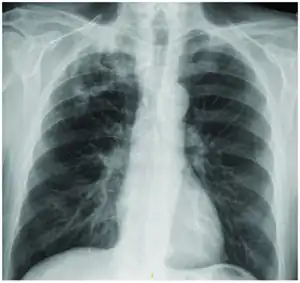

According to the medical literature Mycobacterium interjectum can cause the following:[1]

- Lung infection